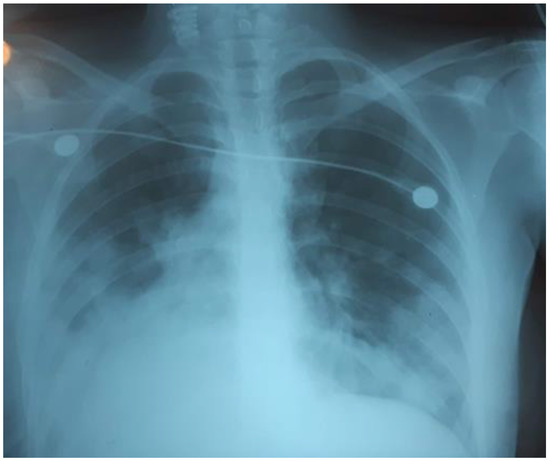

Severe Coronavirus HCoV-NL63 Pneumonia in a Patient Receiving Blinatumomab with Secondary Antibody Deficiency in COVID-19 Times

by Claudia C. Paredes-Amaya, Lorena Matta-Cortes and Andrés Felipe Zea-Vera

Introduction: Human coronavirus NL63 (HCoV-NL63) is one of four common human respiratory coronaviruses. It causes lower respiratory tract infections in young children, elderly and immunosuppressed people, which could result in fatal outcomes. In this time of pandemic, we want to highlight the importance of other coronaviruses infection besides SARS-CoV-2, especially in a patient with underlying conditions like acute lymphoblastic leukemia, receiving immunosuppressive therapy that could result in humoral secondary immunodeficiencies. Case report: We present the case of a 44-year-old Colombian man with acute lymphoblastic leukemia who developed HCoV-NL63 pulmonary infection after the first month of treatment with blinatumomab complicated with severe secondary hypogammaglobulinemia. HCoV-NL63 was detected by multiplex PCR, and HCoV-NL63 viral pneumonia was diagnosed. Hypogammaglobulinemia was studied by determining serum immunoglobulins levels and protein electrophoresis. The treatment consisted of supportive therapy and replacement with intravenous immunoglobulins. After therapy, the patient improved his oxygenation, and the infection was resolved in a few days. Conclusions: This case highlights the relevance of other coronaviruses infections besides SARS-CoV-2 in patients receiving immunosuppressive therapy who develop secondary antibody deficiency, and the importance of replacement therapy with intravenous immunoglobulins at early stage of infection with HCoV-NL63. Full article

Show Figures